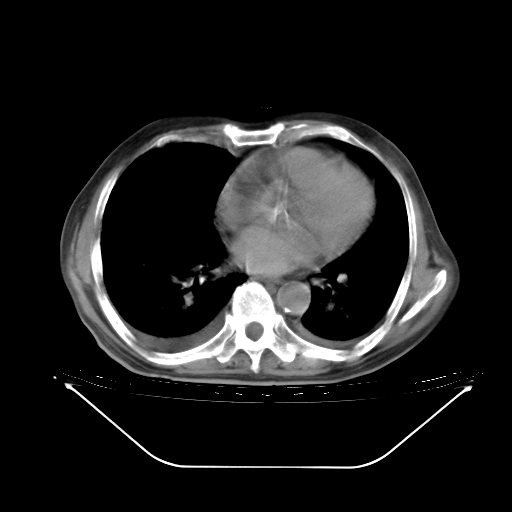

胸腹部CT,诊断意见:左上肺叶钙化灶、左侧胸膜局限性增厚并钙化、胆囊炎。描述部分肺组织呈磨玻璃样改变。